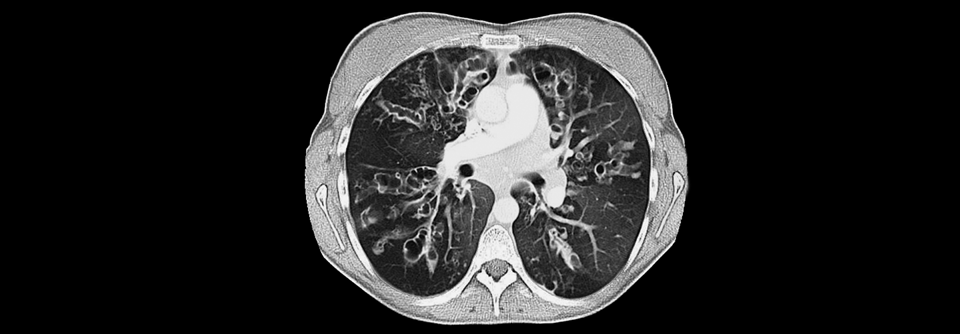

Die Lungenerkrankung steht meist im Vordergrund und ist Hauptgrund für die Mortalität. Der visköse Schleim auf den Epithelzellen der Bronchialschleimhaut beeinträchtigt die mukoziliäre Clearance und verengt die Atemwege. Die Kolonisierung der Atemwege durch pathogene Keime wird dadurch begünstigt. Besonders gefürchtet ist die Besiedlung mit Pseudomonas aeruginosa. Diese Keime können in eine mukoide Form mutieren und bilden Biofilme, wodurch sie vor dem körpereigenen Abwehrsystem und Antibiotika geschützt sind. Durch die chronische Inflammation und rezidivierende Bronchitiden und Pneumonien wird das Lungenparenchym im Verlauf irreversibel geschädigt, was letztendlich die Lebenserwartung begrenzt.

•  Im Verlauf Bronchiektasen und obstruktives Emphysem

•  Fibrose mit pulmonaler Hypertonie und respiratorischer Insuffizienz im Spätstadium

• Bildgebung des Thorax